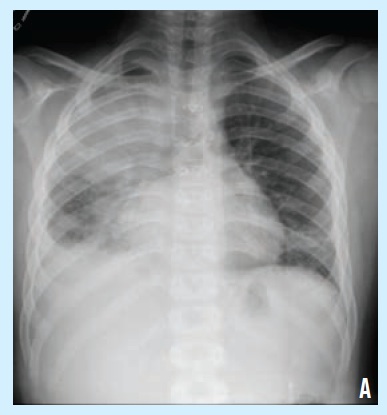

A 9-year-old boy presented to a pediatric hospital for evaluation of fever, cough, and nasal congestion that had been present for 4 days.

M pneumoniae infections typically are mild but can be associated with a mucositis similar to that seen with SJS.